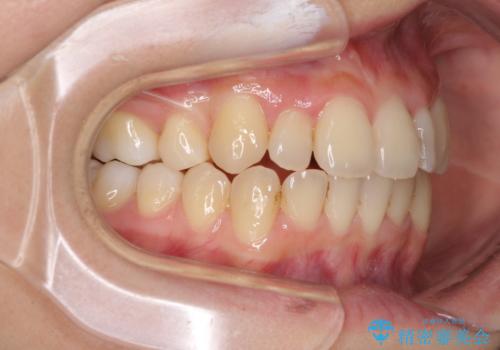

八重歯の抜歯矯正 補助装置を用いたインビザライン矯正

- 上顎の重なっている前歯を気にして来院された患者様です。

重なっている部分は抜歯が必要で、歯の移動量が多く、更には右側にずれている正中を改善する必要がありました。

インビザライン単体での治療は困難と判断し、補助装置により八重歯移動後にインビザラインを用いることとしました。

非常にしっかりとマウスピースを装着してくださいましたが、前歯の排列がなかなか仕上がらずに期間がかかってしまいました。